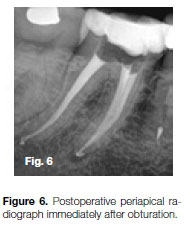

Figure 6 shows the final result after glide path preparation with a ProGlider (Dentsply Sirona), canal preparation with a Primary WaveOne Gold (Dentsply Sirona) instrument and canal obturation with gutta-percha and Pulp Canal Sealer (SybronEndo, Orange, California) using warm vertical condensation technique.